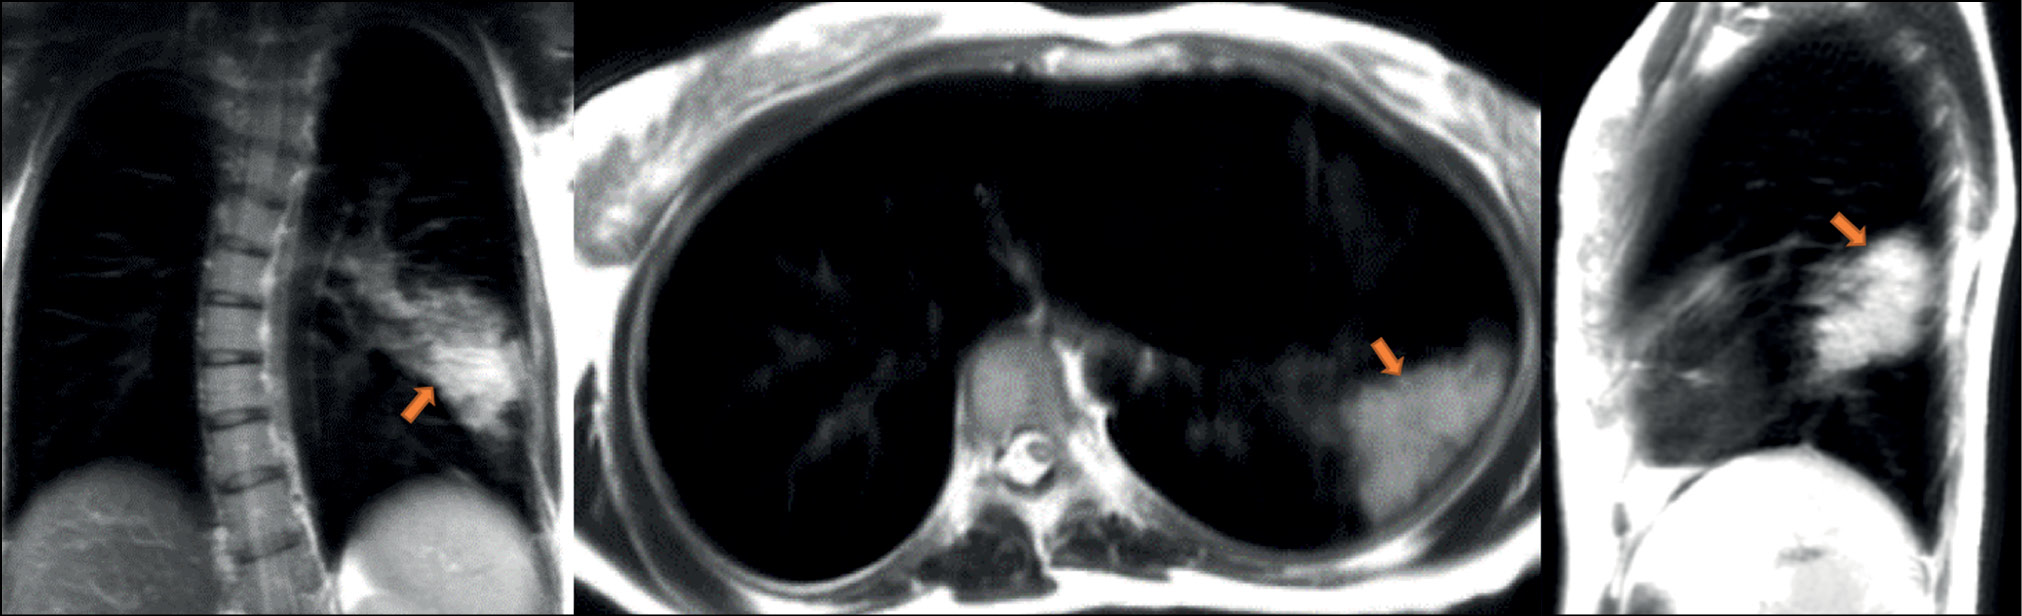

A patient (female, 45 years old) presented to the clinic on the fifth day after the onset of dry cough and mild fever up to 37.5°С. Dynamic lung MRI in the coronal plane (Fig. 1) showed an area of hyperintense signal in the lower lobe of the right lung (S9–S10), interpreted as an area of central induration (more intense signal) with a surrounding “cloudy sky” (less intense signal) during inhalation. A hyperintense signal was found in the corresponding area in the axial and sagittal planes, indicating consolidation with a “cloudy sky” along the edge of the area. At the end of exhalation, increased signal intensity was observed in the described area in the coronal plane (Fig. 2) with decreased visual size of the affected areas due to lung tissue contraction. During exhalation, no changes in signal intensity were observed in the axial and sagittal planes.

Figure 2. Dynamic magnetic resonance imaging of the lungs during exhalation in the coronal, axial, and sagittal planes. Arrows indicate the areas of consolidation (S9–S10).

If the same hyperintense signal is observed regardless of respiration phases, this could indicate alveolar infiltration (consolidation), but a less intense signal during exhalation could indicate intermediate changes (cloudy sky”).